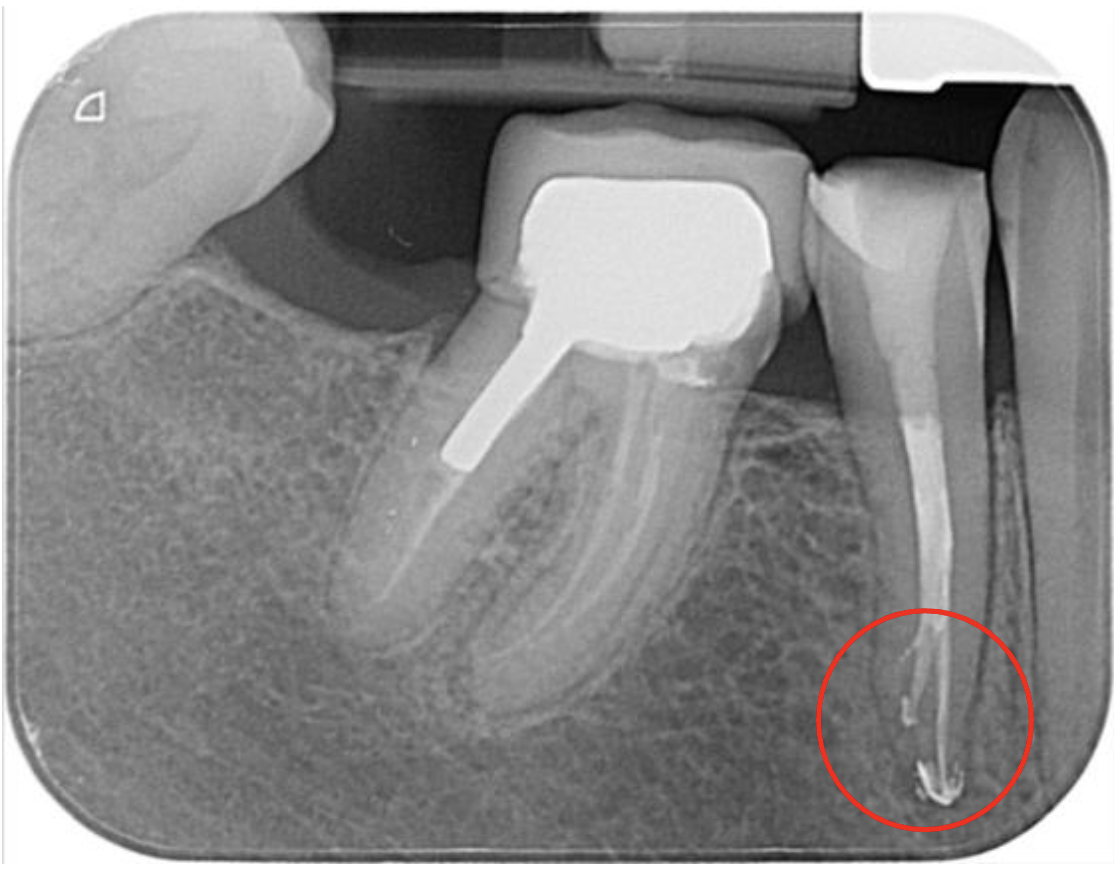

This Vertucci type V LR4 case had been previously initiated by the referring dentist (RD) and displayed minimal apical change on the pre-op IOPA.

Once I had carried out a consultation and taken my own IOPAs, including a mesial angle shift, I felt the root treatment had an excellent chance of success for this tooth. Usual local anaesthetic rubber/liquid dam protocols were used. The tooth was reaccessed using a combination of ultrasonic access tips and LG burs to improve straight-line access to the deep-lying apical split. Preparation was completed using Dentsply’s Reciproc Blue R25 file using lengths calculated from the Morita ZX apex locator (zero readings -0.5mm). Copious irrigation was performed with 5.25% NaOCl and 17% liquid EDTA.

All irrigants were activated using passive ultrasonic irrigation (PUI) with Eighteeth’s Ultra X. It was then filled using a combination of warm vertical compaction (WVC) and AH+ resin-based sealer. 3M’s Filtek’s bulk one resin was used as a nayyar core. This lovely lady was then returned to her RD to provide cuspal coverage.